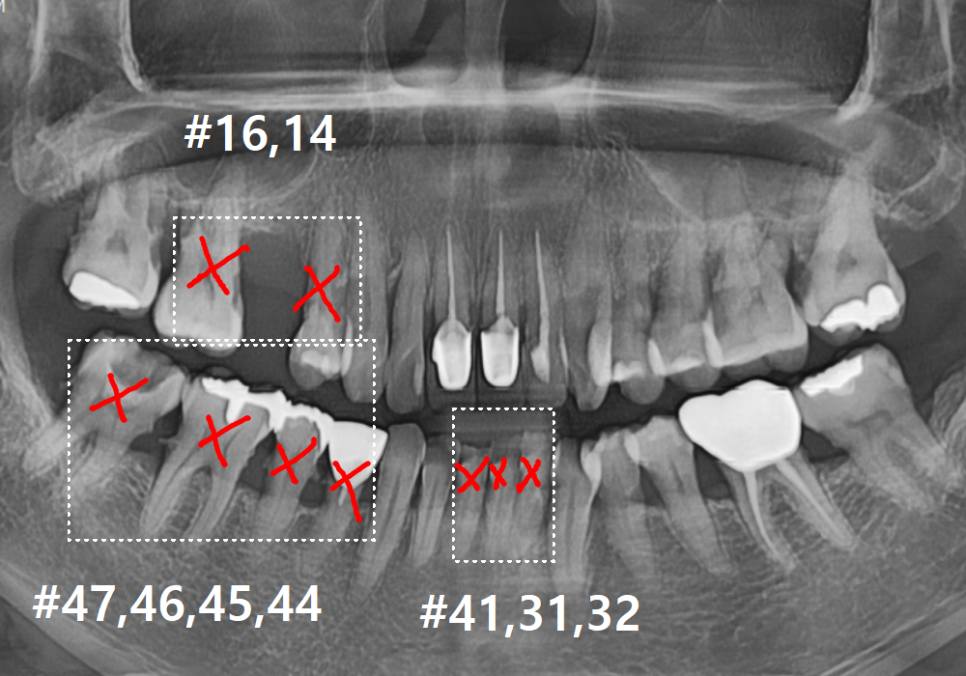

방사선 사진을 살펴볼게요~

매끈해보여야 할 치아 뿌리 쪽에

돌기처럼 무언가 붙어있는게 보이시나요?

251201

바로 치석인데요.

#47 치아: 수직 파절(완전히 쪼개짐)

#47,46,45, #31,32,33, #16,14 : 치아흔들림

전체적인 상태: 잇몸뼈가 녹아

치조골 수평이 매우 낮아진 상태

치료 계획

단순히 치아 하나를 치료해서

될 상황이 아니었기에,

전체적인 재건 계획을 세워드렸습니다.

1 ) 발치 (#16,14, #37,36,35,34, #41~32)

흔들림이 심해 살릴 수 없는 앞니와

어금니들을 발치했습니다.